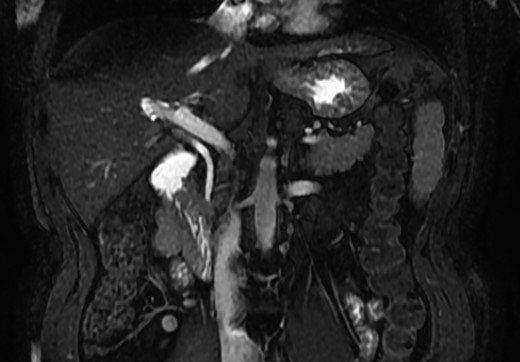

A magnetic resonance cholangiopancreatography (MRCP) confirmed the absence of gallbladder and of the cystic duct and artery (Figs 4–6). No other abdominal anomaly was identified.

MRCP showing biliary tract with GA and no other biliary anomaly; duodenum and the main pancreatic duct are also with visibility; AHB, anterior hepatic branch.